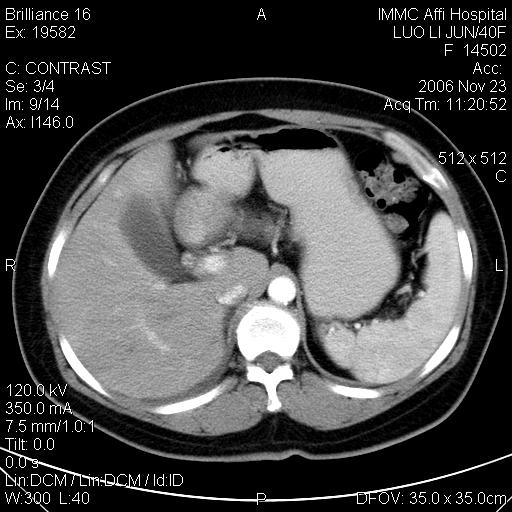

标题: CT5664:我也发一个肝脏的片子大家看看

很典型的肝癌。

速升速降,典型肝癌.

支持-----考虑肝癌----[-从片上看增强早期应该是动脉晚期即门脉早期]

是啊,典型的早出早归!

快进快出典型肝癌.

符合肝癌的增强特征。支持肝癌!

病灶好圆!可能恶性度不高。

很好的片子,可惜增强做的比较失败,a期时间没有把我好,实际到了静脉早期了,否则会更典型。

最终考虑是肝腺瘤